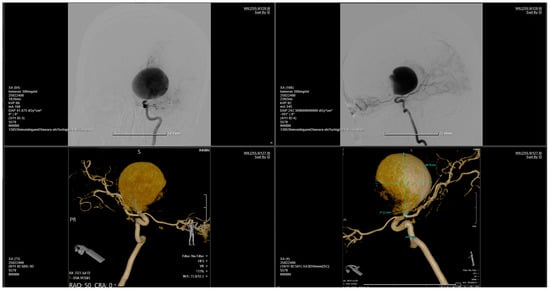

Figure 4.

Series of 2D digital subtraction angiographies that highlight the Coanda effect [1]. The contrast substance tends to adhere to the walls when first entering the aneurysm—as the arrows show—and continues to follow the walls, as seen in the series of chronological images—from 1 to 8. [2]. This phenomenon also creates small vortexes inside the aneurysm, vortexes which are common findings during regurgitative valvopathies in cardiology [3].